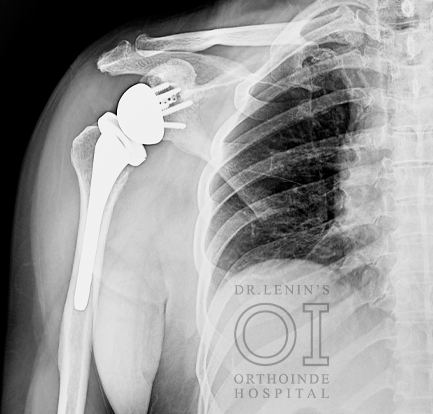

Reverse Shoulder Replacement

In a reverse total shoulder replacement, the rounded head of the upper arm bone is removed Using screws and special tools, and a plastic socket is attached to the remaining bone. The socket of the shoulder blade is also removed and is then replaced with a metal ball.